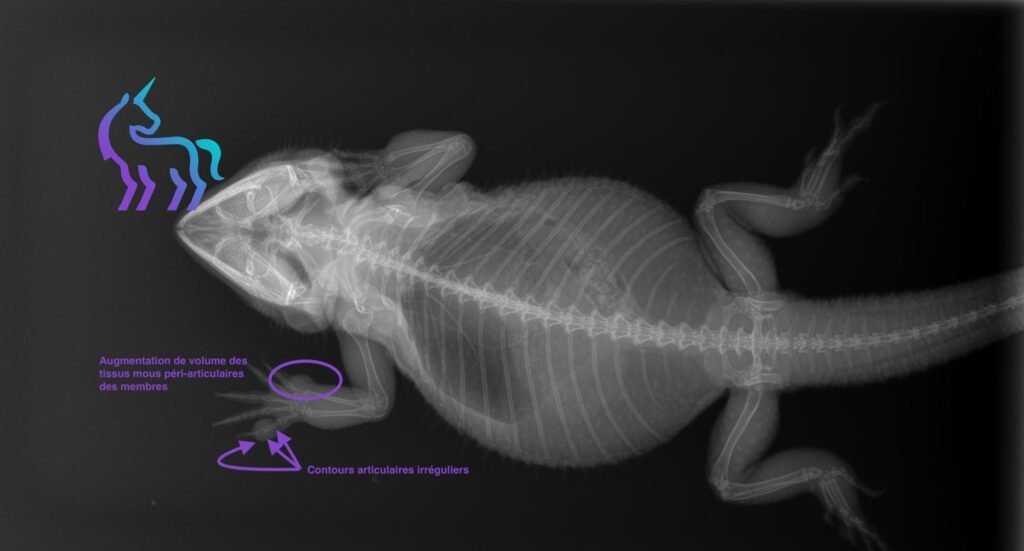

À découvrir : La Goutte du Pogona Goutte articulaire : un mal insidieux chez le lézard Un œdème des pattes,